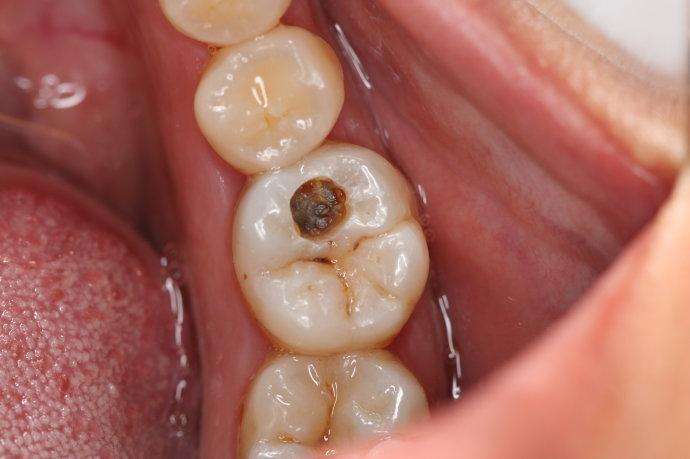

第一阶段:牙齿咬合面有黑线,大牙一般最常见,说明开始蛀牙了,牙釉质被细菌龋坏,但不痛不痒,会出现窝沟龋得及时补牙,而不是去洗牙;

第二阶段:牙齿出现小黑洞,说明引起中度蛀牙,细菌腐蚀来到牙本质,伴随着牙齿敏感,黑色腐败物质其实就是细菌的产物,这时候还可以再补牙;

第三阶段:牙齿超过一半烂掉,说明已经重度蛀牙,细菌伤及牙髓牙神经,还伴随着剧烈疼痛,牙神经病变这时得根管治疗处理,挽救伤痕累累的牙齿。